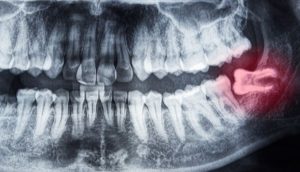

歯根破折と

診断をお受けになった場合には

歯根破折は

どこで歯の根っこが折れているのか

によって

歯を残すことができるのか

歯を抜かなくてはいけない状態なのかが

わかります。

歯根破折がどの程度なのか?

どこで折れているのか?

抜かずに処置できる程度なのか?

その見極めが大事です。